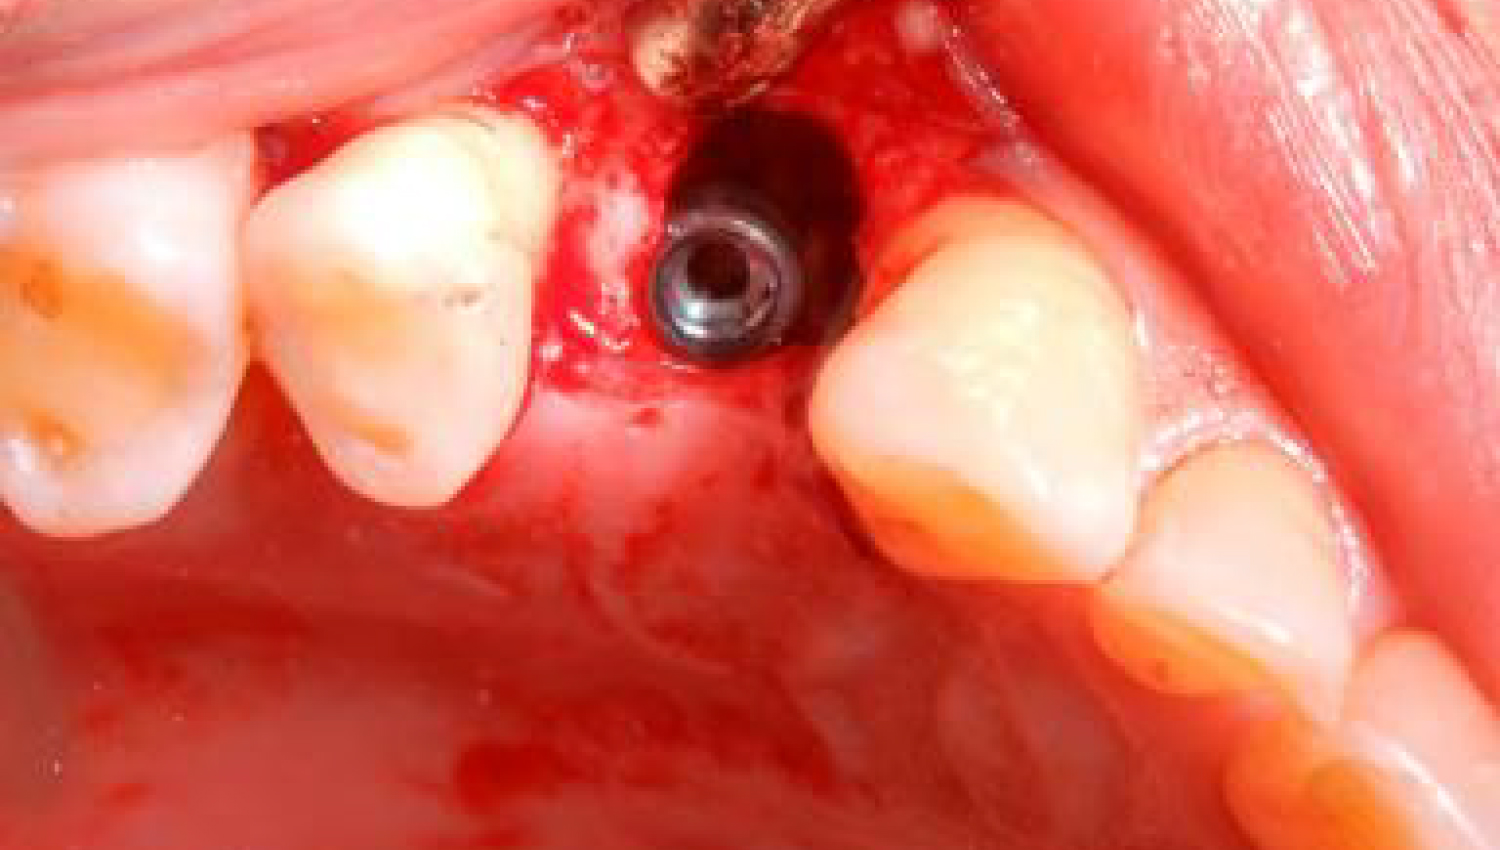

2.The implantation procedure is performed..jpg)

3.Powerbone granule is applied to increase bone regeneration around the implantation.